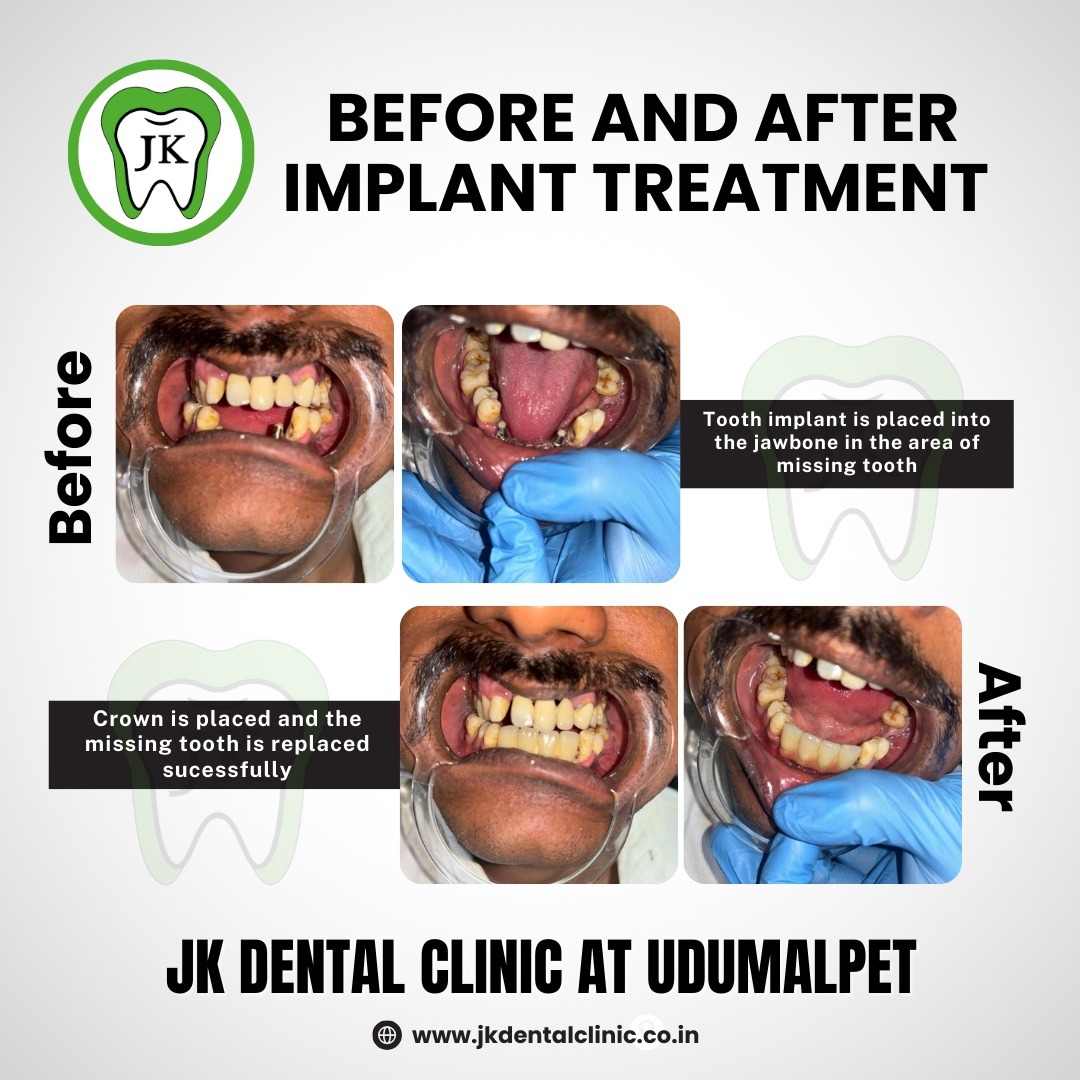

Implants

Root Canal Therapy | Impaction / Extraction | Orthodontic / Braces | Crown & Bridges | Dental Implants | Complete Denture (BPS) | Gum Surgeries | Full Mouth Rehabilitation | Filling & Restoration | Scaling & Polishing | Kids Dental Care | Smile Designing & X Ray

JK Dental Clinic and Implant Centre in Udumalaipettai provided me with excellent care when I went there for crown capping and implants. I was pleased with the procedure and am extremely happy. The JK dental clinic and its staff are also highly recommended. Thank you so much